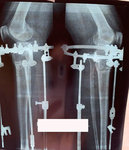

Исходник - 48 лет.

Диагноз: варусная формация голеней.

Дата операции - 17.10.2019г.

на фиксации